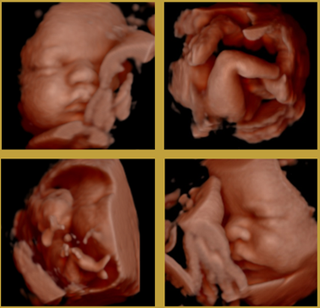

In Rotterdam zijn verschillende soorten echo's beschikbaar voor diverse doeleinden, zoals het controleren van de gezondheid van de baby, het meten van de groei en het bepalen van de ligging in de baarmoeder. De meest gebruikelijke soorten echo's zijn de 2D-, 3D- en 4D-echo's, elk met hun eigen unieke kenmerken en voordelen. Deze echo's worden gedaan door deskundige professionals in medische centra en ziekenhuizen in Rotterdam, waar de zorg van hoge kwaliteit is en de patiënt centraal staat. Naast de reguliere echo's zijn er ook specifieke echo's zoals de groei-echo en de liggingsecho, die extra informatie kunnen geven over de ontwikkeling van de baby.

- De verschillende soorten echo's die beschikbaar zijn in Rotterdam, zoals de 2D, 3D en 4D echo

In Rotterdam zijn diverse soorten echo's beschikbaar voor verschillende doeleinden, zoals het monitoren van de gezondheid van de baby, het meten van de groei en het bepalen van de positie in de baarmoeder. De meest gebruikelijke echo's zijn de 2D-, 3D- en 4D-echo's, elk met hun eigen unieke kenmerken en voordelen. In medische faciliteiten en ziekenhuizen in Rotterdam worden deze echo's uitgevoerd door deskundige professionals, waarbij hoogwaardige zorg voorop staat en de patiënt altijd op de eerste plaats komt. Er zijn naast de reguliere echo's ook gespecialiseerde echo's beschikbaar, zoals de groei-echo en de liggingsecho, die gedetailleerdere informatie kunnen geven over de ontwikkeling van de baby.